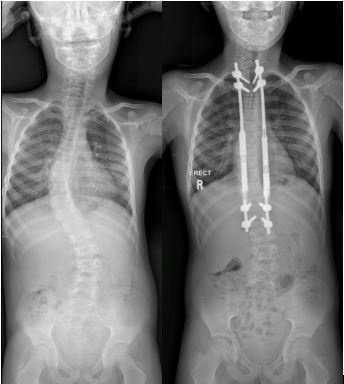

As with anything else in nature, the growth and development of the spine may not always go according to plan. Early onset scoliosis is sometimes caused by congenital anomalies, syndromic etiologies or neuro-muscular causes, such as cerebral palsy or muscular dystrophy, and results in young children seeing the side-to-side deformity of the spine developing before the age of 10.

If left unchecked this potentially devastating condition results in severe spine and chest wall deformity through growth. This in turn may result in lungs that are underdeveloped in terms of functionality. In the long term, thoracic insufficiency syndrome may occur – a condition with cardiorespiratory compromise and a diminished life expectancy.

According to Dr Davis, there are a number of surgical options to consider if conservative modalities fail, or are not deemed appropriate. Each of these carry their own difficulties and potential problems. “The universal theme is one of guided or controlled growth, where we allow the spinal column to lengthen through normal growth. The curvature of the spine is controlled, limiting the progression in deformity until we have seen adequate growth to allow near normal (functional) respiratory capacity. At this point a definitive fusion procedure can be done, allowing for a final and permanent solution.” To facilitate this controlled growth for young patients, innovative solutions are required.”

Magnetic growing rods are part of this group of innovative solutions. “While they are relatively well established internationally now, I was the first to use magnetic growing rods in South Africa (June 2017) in Stellenbosch, and currently have a number of the children with early onset scoliosis being treated, both in my practice and at Tygerberg Academic Hospital with this modality,” explains Dr Davis.

A magnetic growing rod consists of single or dual titanium spinal rods that contain a magnetically drivable lengthening mechanism. The outcomes of these growing rods are favourable in certain aspects compared to the traditional growing rod technique, where open surgical lengthening had to be performed every six months. Implant associated complication (breakage) rates are similar: however infection risk and number of surgical interventions and anaesthesia events are significantly less. This helps with the treatment of a specific patient group with a condition that is very difficult to treat, often with high complication rates, irrespective of the technique used to treat them.